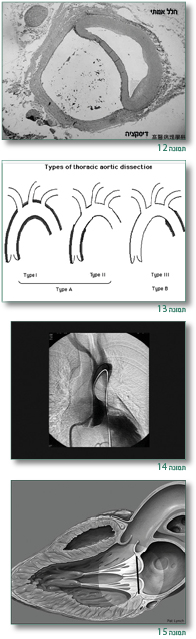

כמו כן הרחבה מתקדמת של שורש אבי העורקים – עלולה להביא לקרע של אבי העורקים (Aortic aneurysm) [שיכולה לגרום למוות מטמפונדה (Tamponade) או איבוד דם] וכן יכולה להיגרם דיסקציה של אבי העורקים (Aortic dissection) (תמונות 12–14).

במקרים שיש מעורבות של המסתם הדו צניפי (Mitral valve) – יש צניחה של המסתם (Mitral prolapse) (יותר שכיח בילדים ובנשים) עם דרגות שונות של דליפה (תמונה 15).